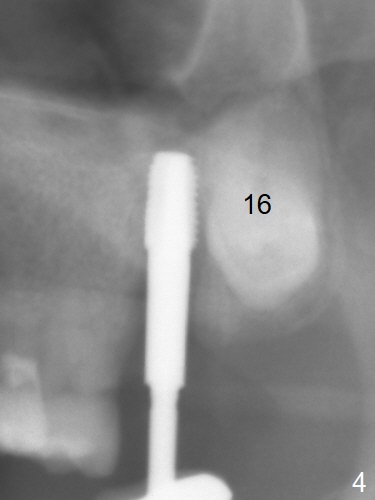

Extraction of the tooth #15 with short clinical crown (suggesting bruxism, Fig.1) reveals a vertical root fracture (Fig.2 <). It seems unnecessary and difficult to create osteotomy in the mesial slope. What can be done is to place starter and 2 mm drills as mesial as possible (Fig.3 (red dashed line: sinus floor). After use of Lindamann bur to move the osteotomy mesially and sequential osteotomy until 3.8x18 mm, a 4.5 mm tap is inserted with clearance from the impacted tooth #16 (Fig.4). A 5x15 mm implant is placed with >60 Ncm with clearance from the 3rd molar (Fig.5,6). If the impacted tooth were removed, the primary stability is expected to be reduced. Impression is taken 6 months postop with 19/20 implants (Fig.7). The bone graft remains in the crestal area immediately and 11 months post cementation (Fig.8,9 *). In the other word, new crestal bone forms after extraction.